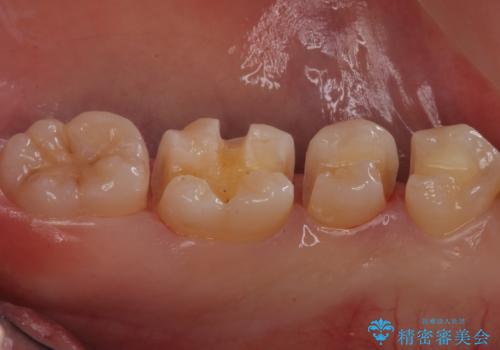

歯と歯の間の虫歯 セラミックインレーでの治療

歯と歯の間に虫歯があったため適合の良いセラミックインレーで修復処置をしていきました。